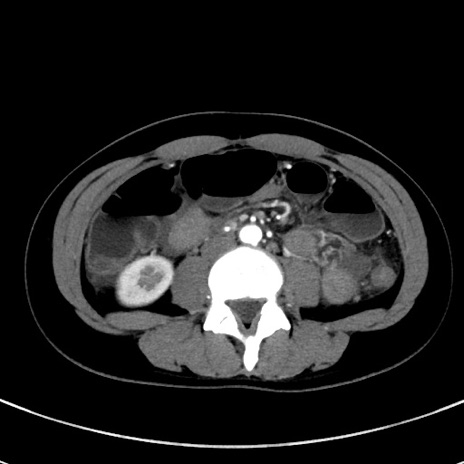

症例17(横断像)

【症例】20歳代女性

【主訴】嘔吐、下腹部痛

【現病歴】昨日夕食後に嘔吐し下腹部痛が出現。本日になっても嘔吐持続し改善しないため来院。

【身体所見】意識清明、BT 37.2℃、BP 108/67mmHg、腹部:平坦、やや硬、下腹部正中から右にかけて圧痛あり、反跳痛軽度あり、tapping pain(+)。

【データ】WBC 13600、CRP 14.94